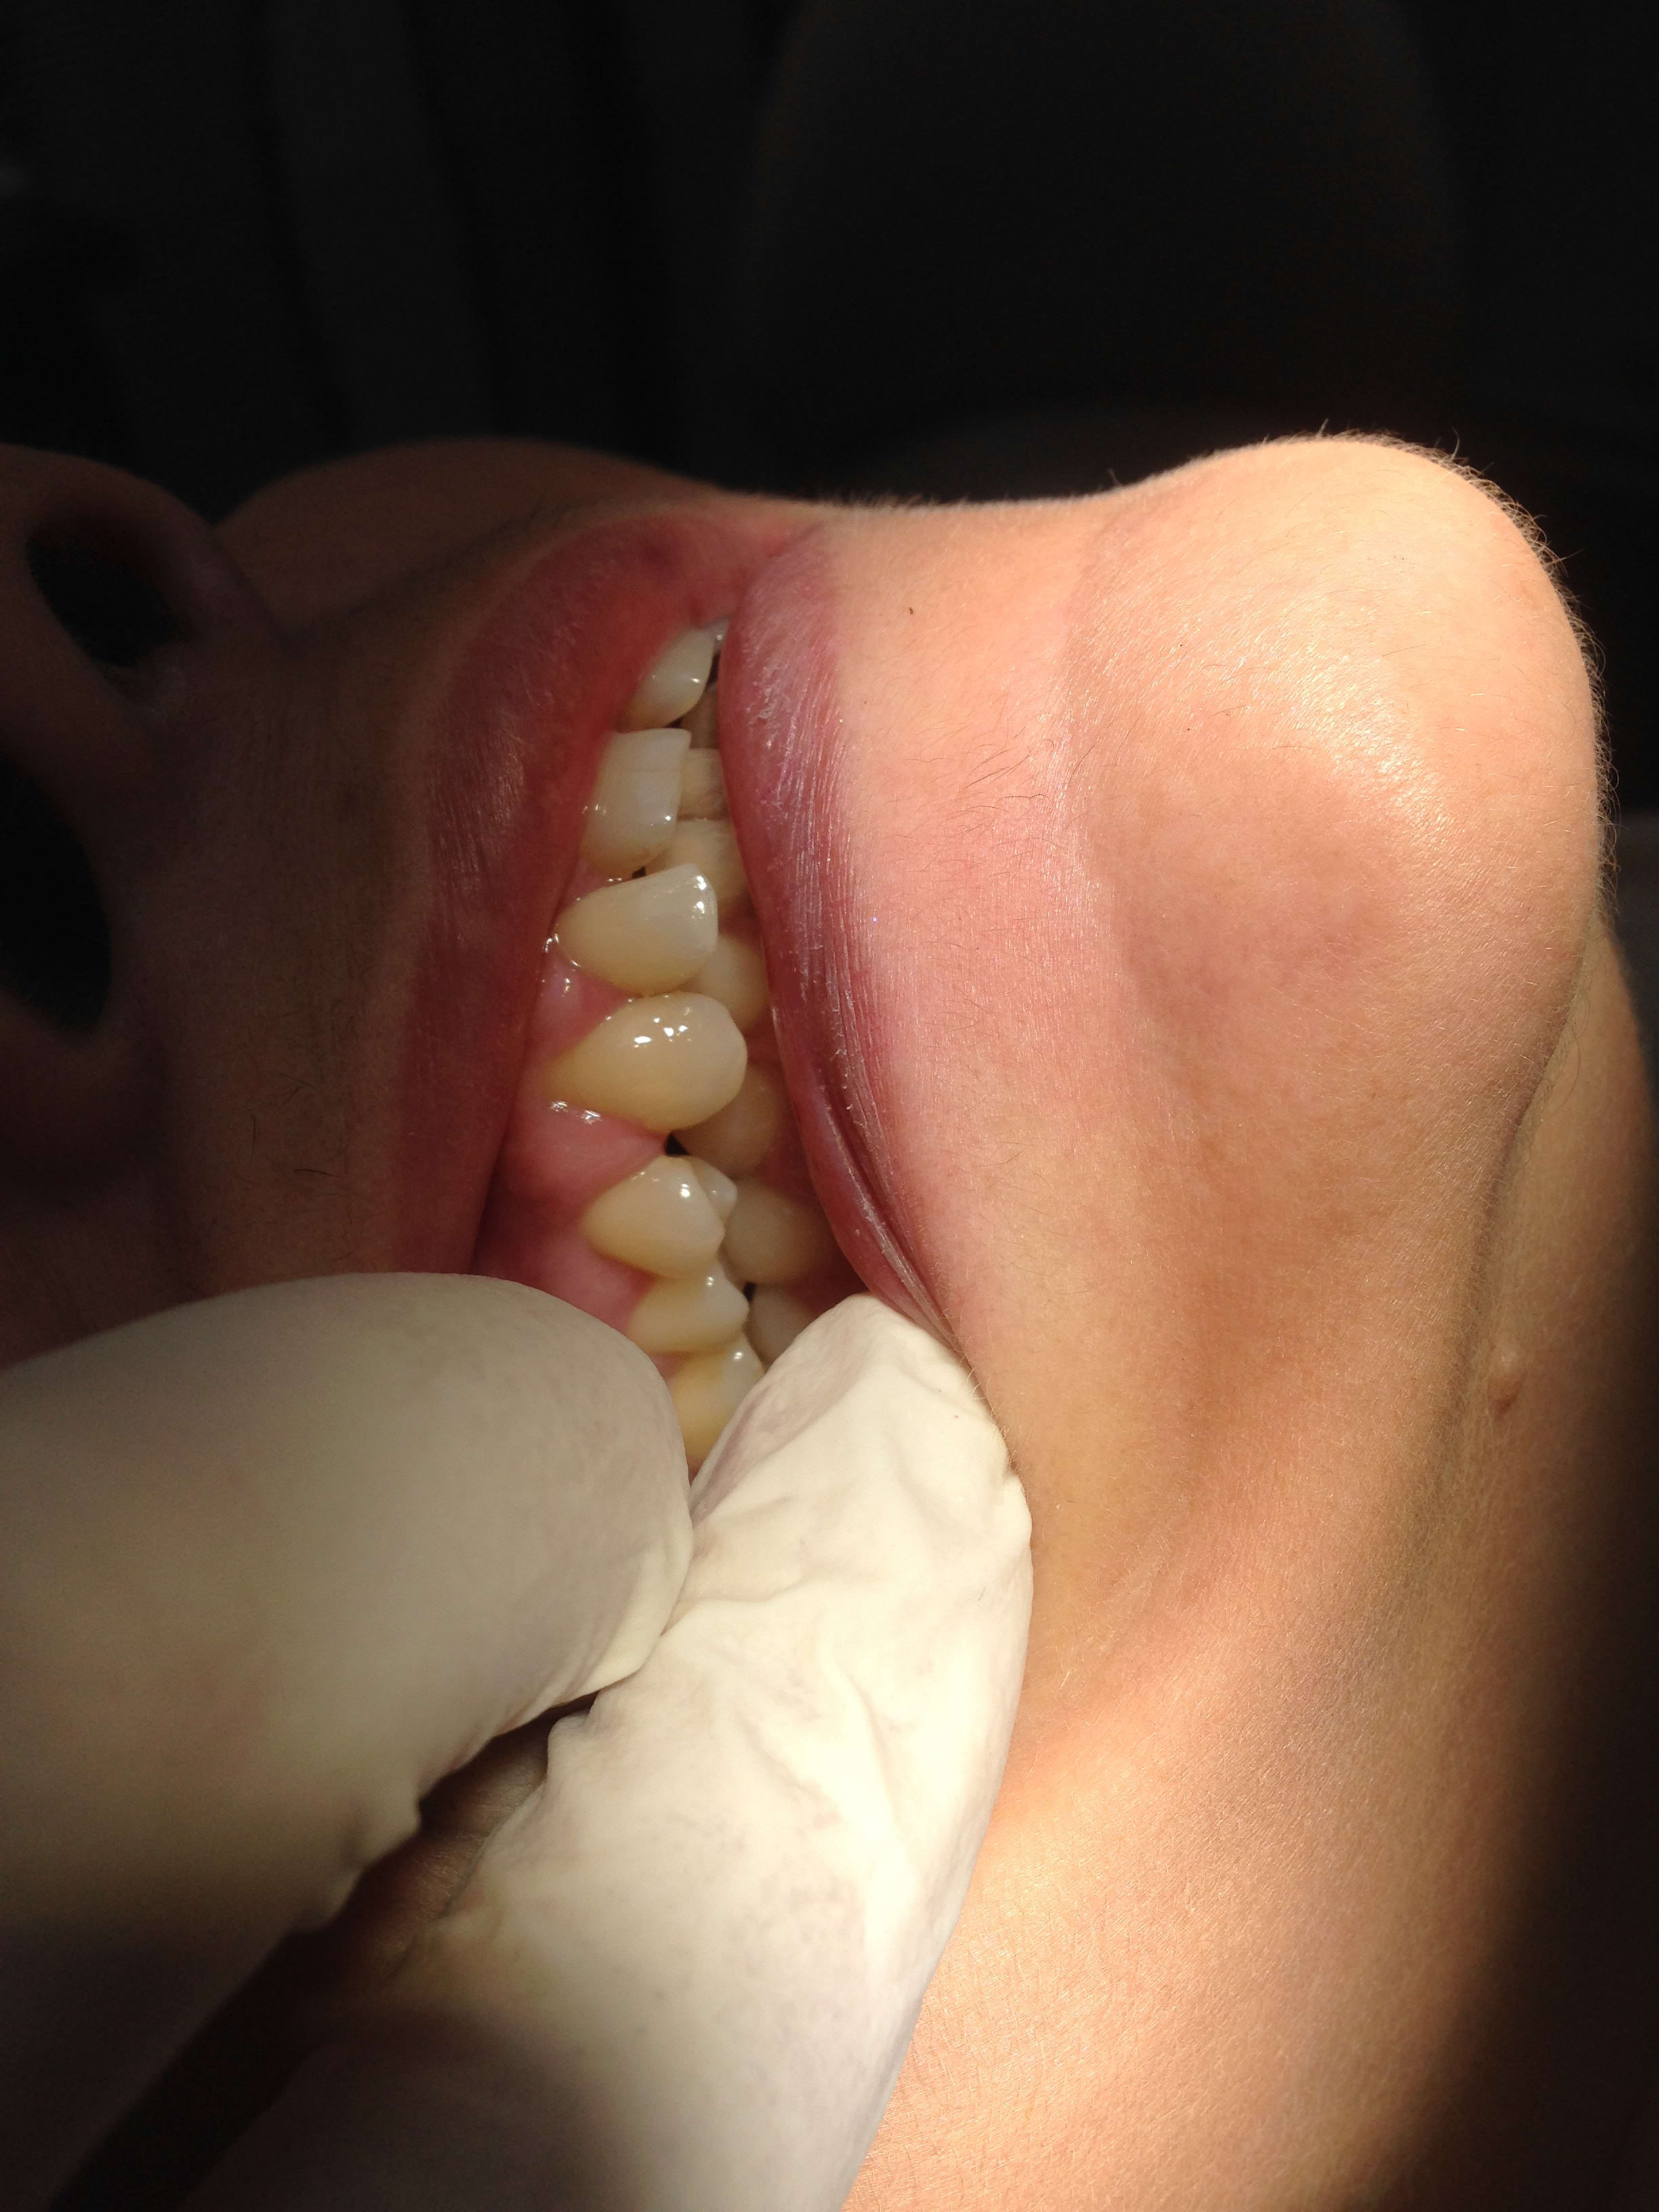

Ah aujourd'hui c'est latex... ça change! Enfin le doigt est tout de même devant :-))

C'est selon les préférences de chacun. Certains préfèrent le doigt devant , d'autres derrière .

Et puis Le but c'est de montrer aussi par la même occasion la qualité des gants chinois 😊